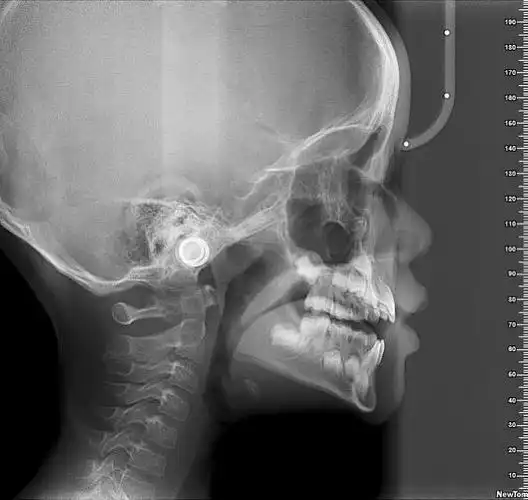

【头颅侧位片】那么牙片的辐射危害大吗?